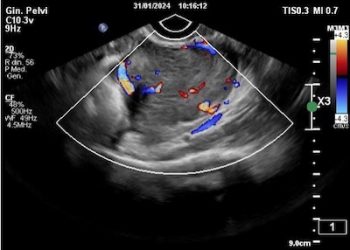

Cari colleghi, vi presentiamo la guida al counseling di Luglio 2024 sul corpo luteo emorragico. Potrete scaricarla cliccando sul link....